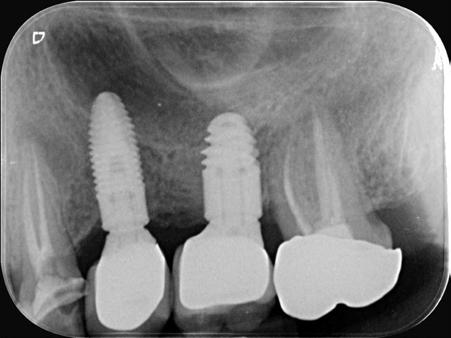

3. Fase quirúrgica final

A los 6 meses de cicatrización, se realizó un nuevo CBCT, obteniendo un nuevo archivo DICOM que alineamos con el STL del encerado. De esta manera, se planificó la posición de los implantes a 4 mm del margen de la restauración final y se diseñó y confeccionó la férula de cirugía guiada dentosoportada en 12-13 y 22-23, la cual imprimimos con la impresora 3D Formlabs®. El provisional

La cirugía se realizó bajo sedación consciente y anestesia local (articaína 4% con epinefrina 40/0,01 mg/ml Ultracain®, 5 carpules en vestibular y palatino de la arcada superior). En primer lugar, se realizaron las exodoncias de los dientes remanentes 11, 21 y 24 y, a continuación, se adaptó la férula de cirugía guiada dentosoportada, insertando los implantes elegidos, en este caso en las posiciones 11 y 21 de Zimvie Tapered Screw-Vent Z3D de 3,7 por 13 mm, 14 Zimvie Tapered Screw-Vent Z3D de 3,7 por 13 mm y 16, 24 y 26 de Zimvie Tapered Screw-Vent Z3D de 4,7 por 13 mm, quedando todos ellos a un torque mayor a 30 Nm. Posteriormente, se realizaron el resto de exodoncias,

Seguidamente, se colocaron los pilares cónicos TSV-TM de Zimmer® y se atornillaron los pilares provisionales de titanio (Figuras 17-23).

Figura 27. Ortopantomografía del provisional atornillado en boca para verificar ajuste.

ortopantomografía de verificación del ajuste pasivo de todos los implantes. Por último, tapamos las chimeneas con teflón y resina provisional y se chequeó nuevamente la oclusión, dando nuevamente las instrucciones de higiene y mantenimiento de la prótesis provisional (Figuras 24-27).